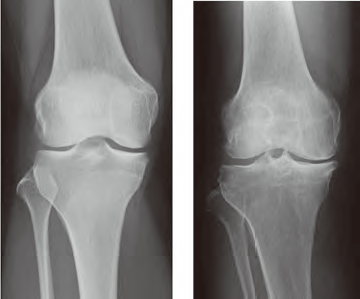

中高年に最も多く見られる膝関節疾患であり、加齢により膝関節機能が低下して、特に軟骨がすり減ることで関節の変形や破壊が徐々に生じる疾患です(図)。肥満や遺伝的素因が原因になることもありますが、骨折や靭帯・半月板損傷などの外傷や感染の後遺症で発症することもあります。

痛みの原因となったエピソードや職歴、スポーツ歴などの問診を行い、痛みの部位や関節の動きを診察します。画像検査としてレントゲン(図)やCT検査、MRI検査でO脚や軟骨のすり減り、関節の変形の程度を評価します。関節リウマチや痛風など他の関節炎の鑑別のために血液検査や関節液検査などを行います。